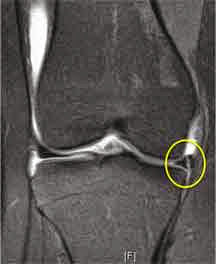

Well, this is a pretty good duplicate of what happened with my knee. A complex tear of the medial meniscus was the diagnosis, but what I THOUGHT was they would do surgery. Uh, no...they said, I'm so sorry. But the tear is in a GOOD place and if we remove it, you will have bone on bone. I was so angry. I just wanted this to be over with. The doctor is supposedly the very best in our area. Her bedside manner, not so much. I couldn't help that tears were rolling down my face after they told me. All she said was, " I know that's not what you wanted." (You think, Doc?) "And we are going to send you to physical therapy and see where we are after that." Lovely.

So, I have had 5 appointments now. And today the therapist informed me I have a dislocated tibia. He moved it back into place, which really hurt, by the way, and then, taped it. It feels much better right now. They are also using a PT therapy for the inflammation of the MCL/Medical Meniscus area called iontophoresis. They use electricity to drive drugs through the skin. The deal is the drug they use has to be ionizable (electrically charged). Dexamethasone is the steroidal anti-inflammatory they use, and yeah, it hurts like a bunch of bee stings. Then it chills out, and begins to feel much better. The therapist finishes with ultrasound therapy. And the jury is still out on what that is supposed to do, but they tell me it promotes healing.